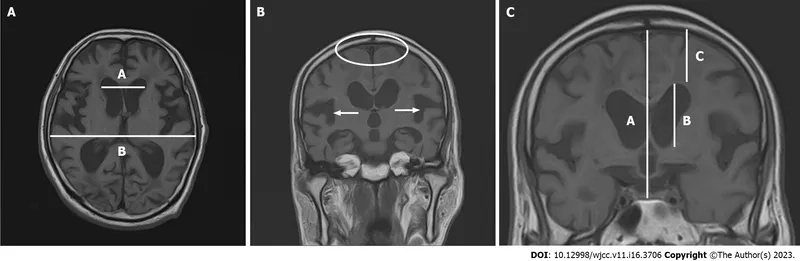

MRI brain scan showing enlarged ventricles in NPH

Understanding hydrocephalus in adults